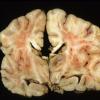

INFECTION

Bacteria

Abscess

Abscess, Subacute - Chronic (6)